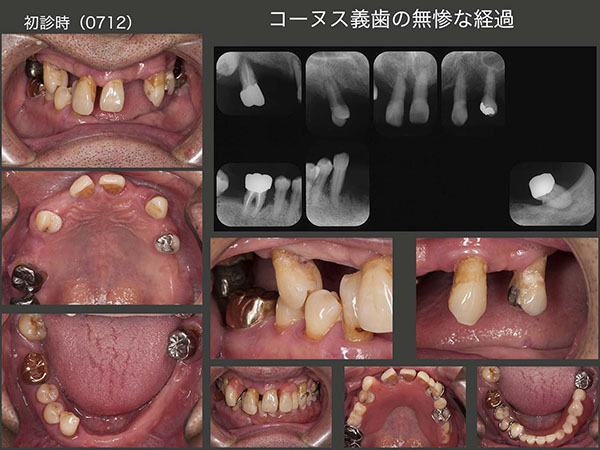

7.コーヌス義歯の無惨な経過

2007年12月初診,67歳男性.義歯が合わないとのことで来院.右側の小臼歯部のみに咬合支持があり,全体に歯周病が進行していた.著しく歯の動揺が大きい右上7および左下8は保存不可能であった.まず義歯の調整,つぎにプラークコントロールの徹底と歯周基本治療に専念した.患者さんはとても穏やかな人で,治療にも大変協力的で歯周ポケットは改善傾向を示した.

コーヌス義歯は順調に推移していたが,2014年頃から異変が生じた.下顎義歯の取り外しがきつくなったため,1ヵ月間,下顎義歯を外さなかったとのことであった.その時はひょっとしてアルツハイマー病の初期ではないかと疑ったが,どうすることもできずそのままになってしまった.その後,症状は経過観察のたびに進行していった.16年になると,奥様に付き添われて来院するようになったが,プラークコントロールもどんどん悪化していった.もうセルフコントロールは無理であったため,奥様にブラッシングしていただくようにお願いした.しかし,16年7月,奥様も疲労困憊といった具合で,下の世話もあり,とても口の中の清掃までは無理と宣告されてしまった.患者さんは遠方からの通院であり,近くでクリーニングをしてくれる歯科医あるいは在宅介護を利用してもらう方が好ましいと考え,そのように説明した.もちろん義歯に関しては私が責任もつと伝えたが,その後連絡はない.患者さんも奥様も本当に良い人で,こちらは何もしてあげられないことに困惑を感じざるを得ない.もう一度,患者さんにお目にかかりたい.